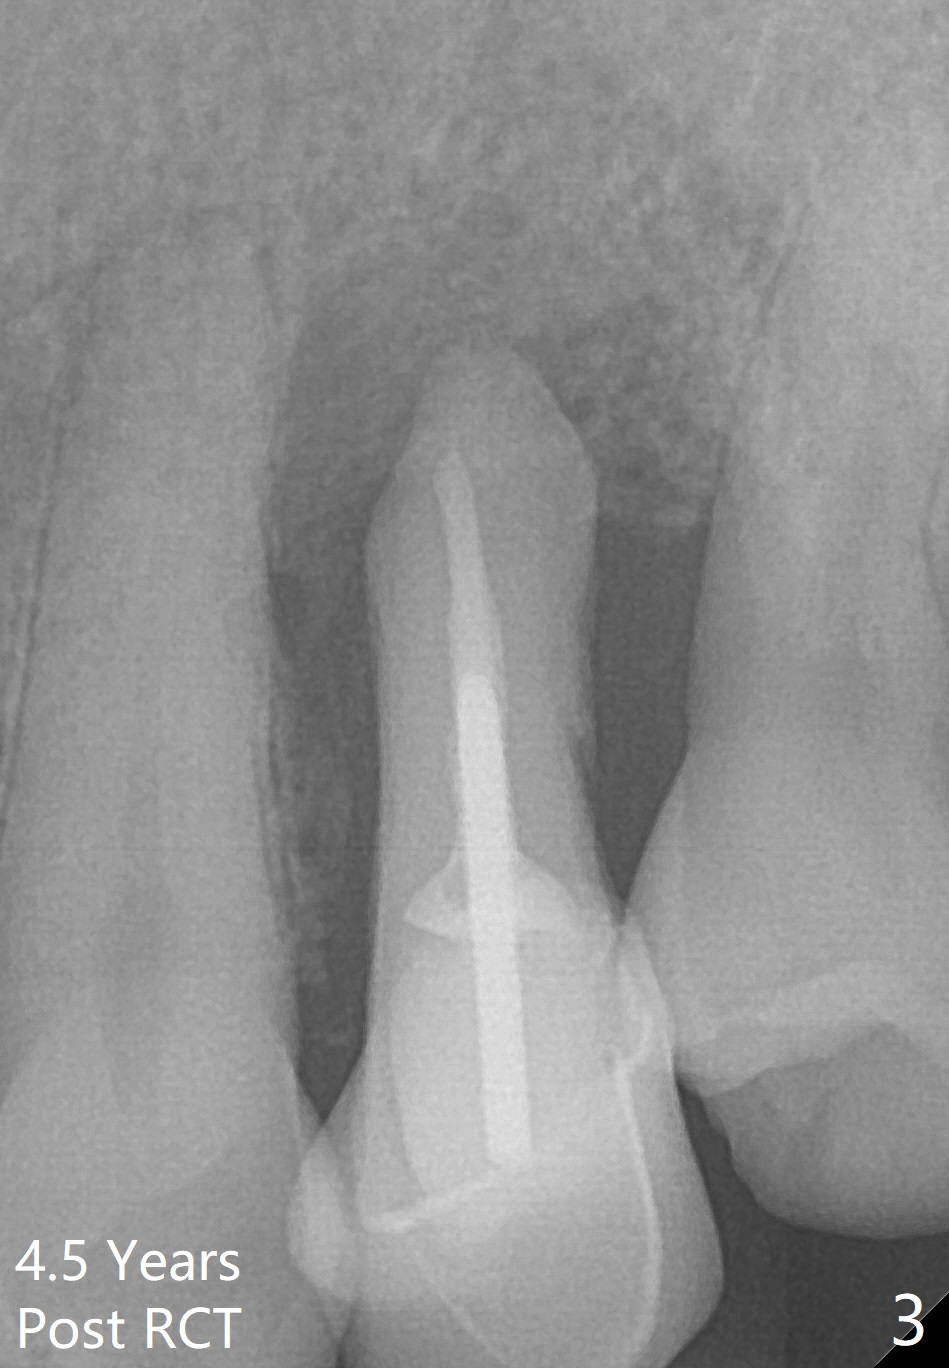

A 61-year-old man with chronic periodontitis presented to clinic for several implant placement (#3 10 14/15 18 30). For the tooth #12 (Fig.1), RCT was rendered (Fig.2). The tooth is non-salvageable 4.5 years post-treatment (Fig.3). Uneven bone loss mesiodistally makes implant placement challenging (Fig.4). A long implant will be used with ~3 mm subcrestal (mesially) and ~3 mm supracrestal (distally). A 3.5 or 4.0x13 mm implant will be placed subcrestal palatally and supracrestal buccally (Fig.5).